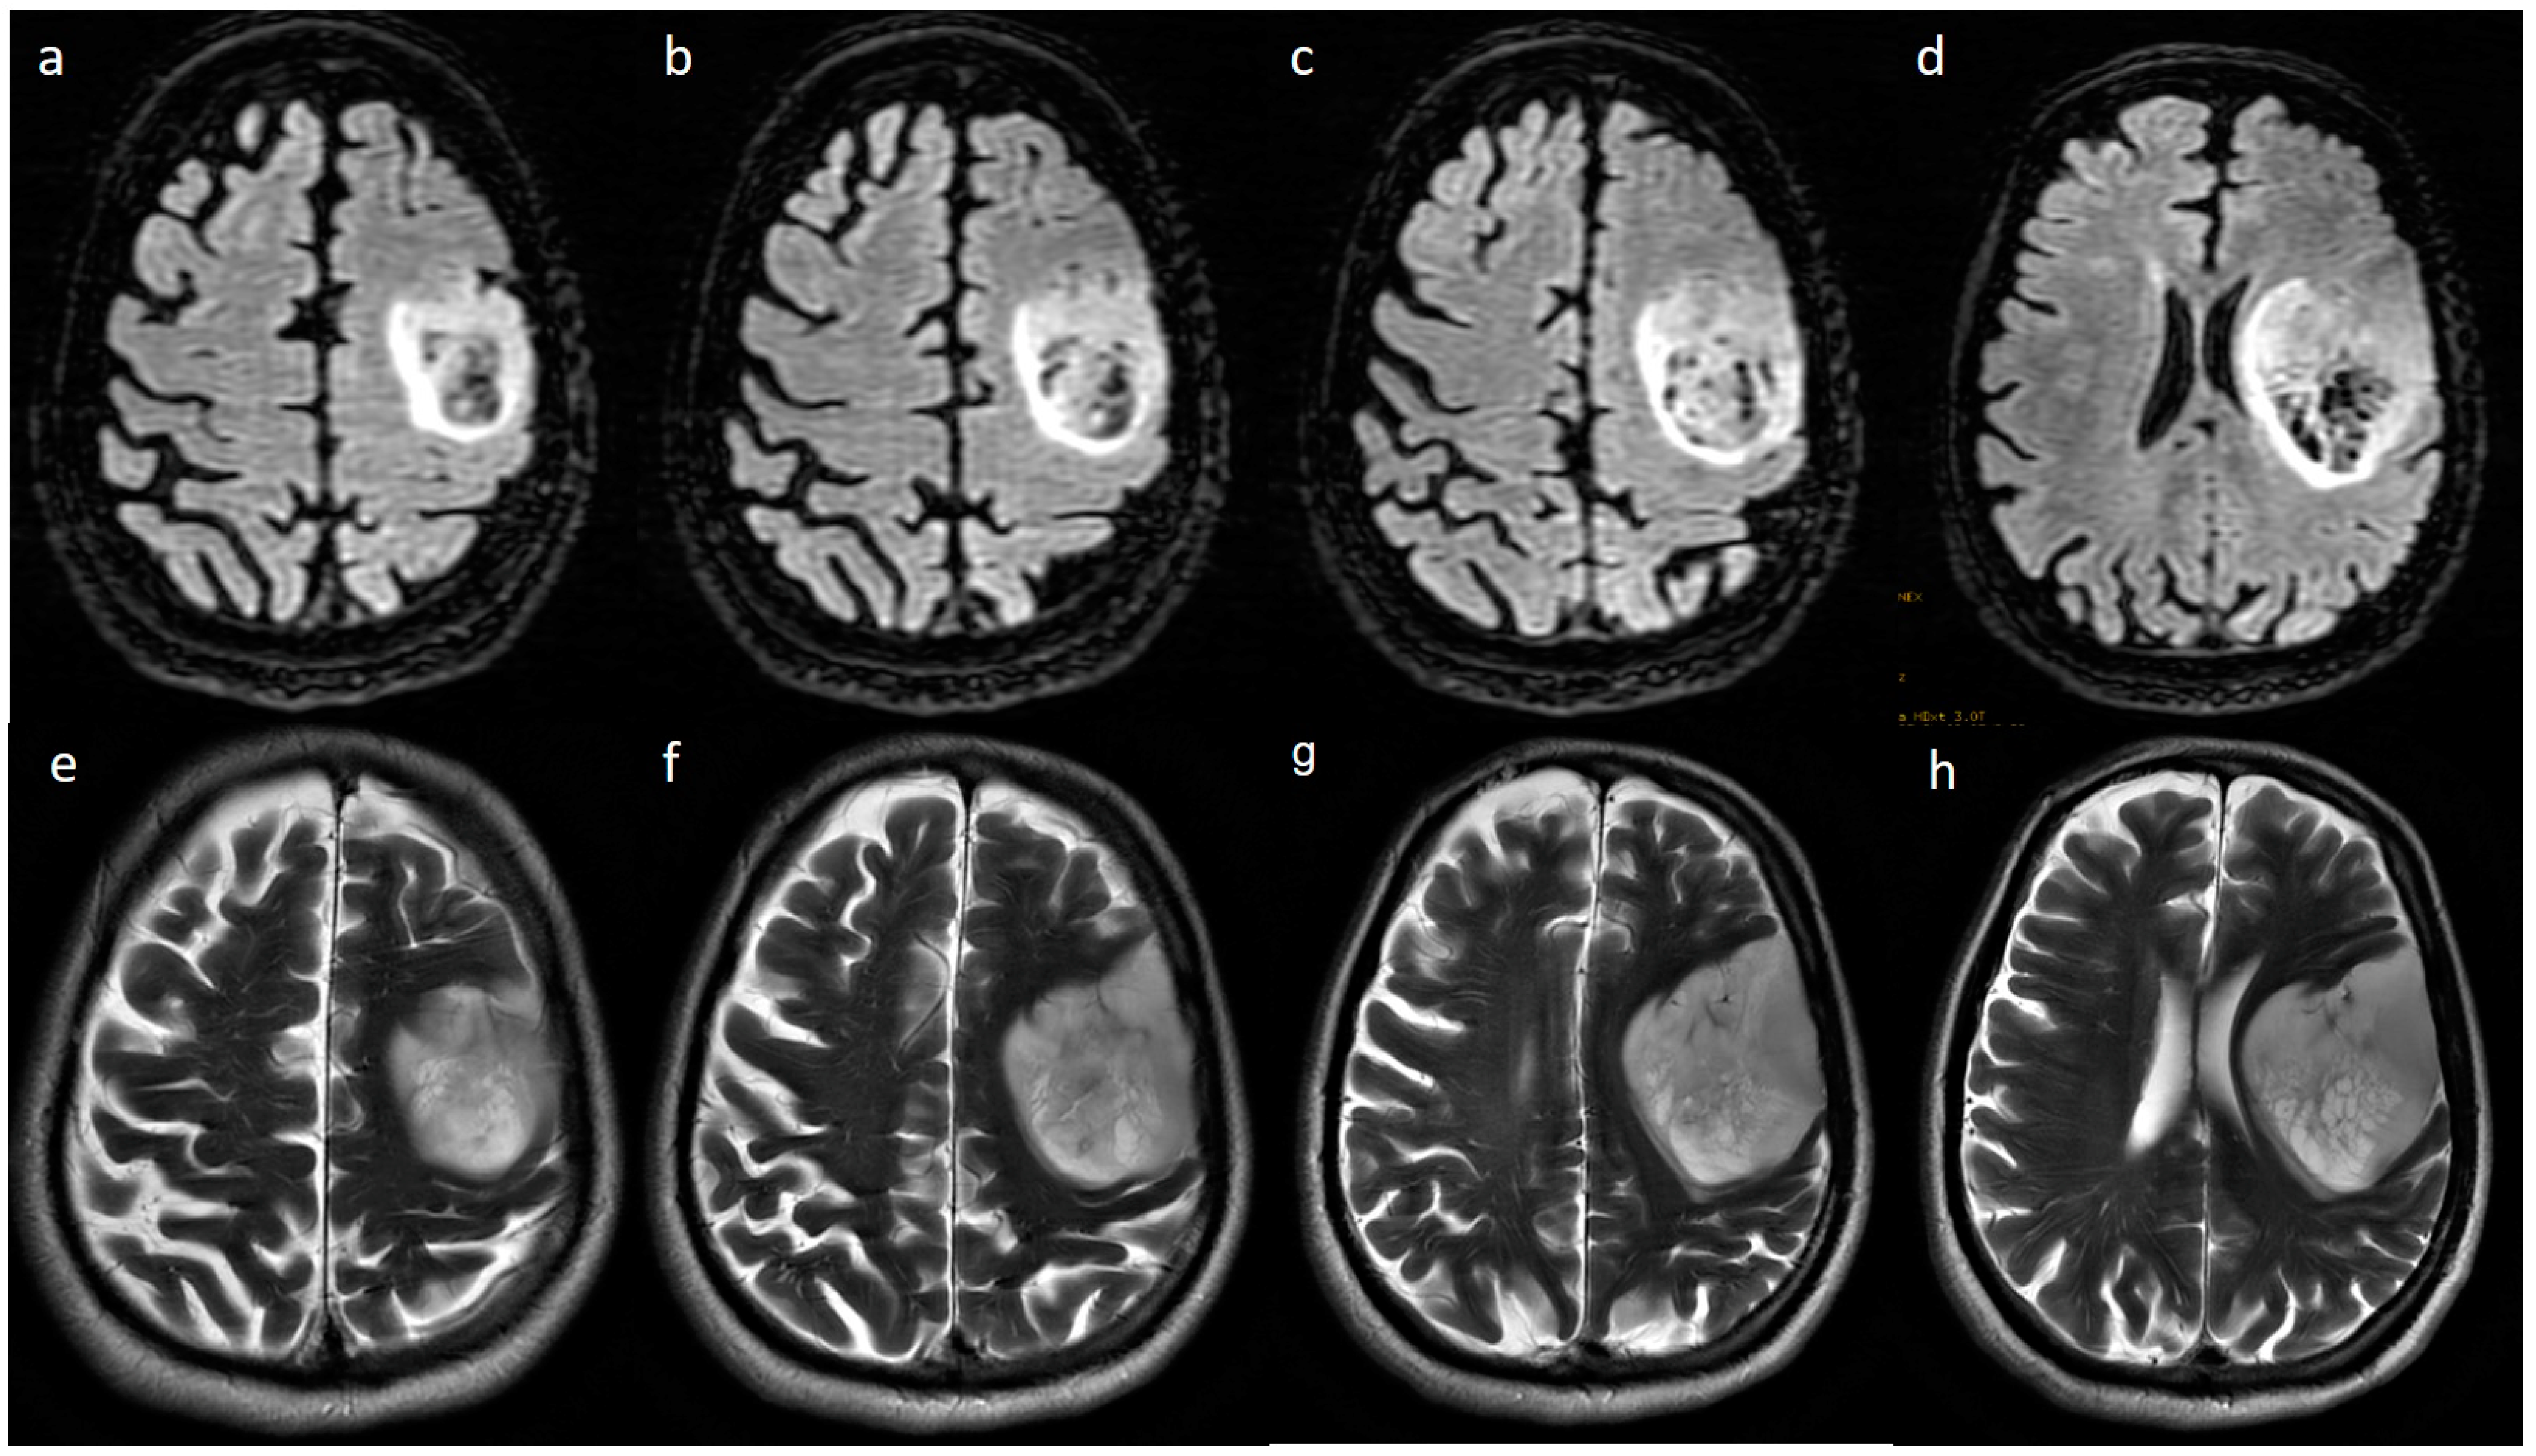

3.2. MRI Parameters of IDH-Wildtype vs. Mutant Phenotype Tumors